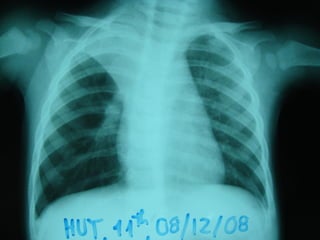

3. X QUANG PHỔI

Có thể BT: 13 % trẻ NV có XQ BT

 DH thường gặp:

 Ứ khí phế nang

 Thâm nhiễm mô kẽ, quanh PQ, PN

 Xẹp phổi: thùy trên phải

 Đông đặc phổi: 24%

 DH hiếm gặp: Tràn khí MP-TK trung thất (1%)

Tràn dịch MP

3. X QUANGPHỔI  Không đặc hiệu: Có thể BT: 13 % trẻ NV có XQ BT  DH thường gặp:  Ứ khí phế nang  Thâm nhiễm mô kẽ, quanh PQ, PN  Xẹp phổi: thùy trên phải  Đông đặc phổi: 24%  DH hiếm gặp: Tràn khí MP-TK trung thất (1%) Tràn dịch MP